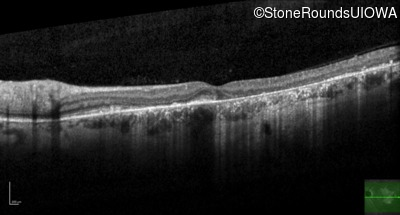

Age at visit: 40 years

Macular Disease WDR19 His344Arg CAT>CGT Ser485Ile AGT>ATT AR